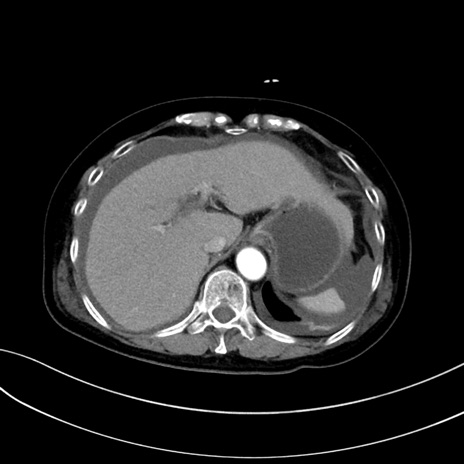

症例13 CT(横断像)1日半後